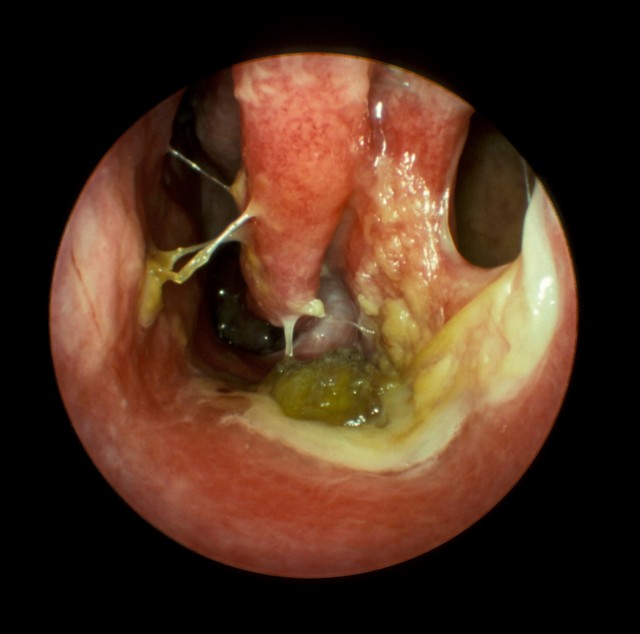

Проблем при постановке диагноза обычно не возникает. ЛОР-специалист оценивает состояние носовых проходов и характер выделений из носа. При извлечении образований из полости невооруженным глазом заметны атрофические изменения. Полость покрыта вязким секретом с резким запахом. Иногда слизистые оболочки бывают разрушены очень сильно.

Врач назначает риноскопию, которая позволяет определить степень поражения носовой полости. Если говорить о возбудителях заболевания, то обычно выделяют два вида патогенной микрофлоры: коринобактерии и клебсиеллу. Какой из возбудителей является провокатором озены в конкретном случае, подскажут бактериологические тесты.

Сложности при диагностике возникают лишь в том случае, если озене предшествуют длительные риниты, а пациент часто проходит лечение в медицинских учреждениях. Тогда заболевания носоглотки переходят одно в другое и нередко носят хронический характер. Микроскопическое исследование позволяет обнаружить метаплазию реснитчатого эпителия оболочки носа. Если патологические процессы затронули глотку, то выявить поражения поможет фарингоскопия.

Для уточнения диагноза может быть назначено эндоскопическое исследование носа. Этот современный метод позволяет под увеличением рассмотреть все изменения слизистой. При необходимости берут мазок из носа для бактериологического исследования, чтобы выявить Klebsiella ozaenae или другие микроорганизмы.